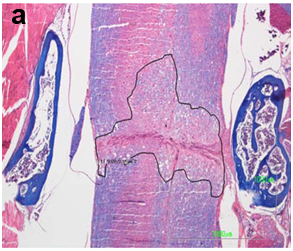

The spinal cord lesion in the mice was asymmetric and did not form a simple cone shape cranially and caudally from the epicenter, as occurs in rats and other mammals. More asymmetric and irregular was the form of restoration of gray and white matter. For these reasons, the extent of the injury was estimated in longitudinal median sagittal sections including the lateral funiculus of white matter, lateral horn of gray matter and central canal. Also, cross sections were also taken as serial sections (Figure 1a&b). The extent of the white and gray matter lesions was measured from the cranial to the caudal boundaries of cyst formation, neural cell damage and white matter demyelination, in Luxol Fast Blue and H/E stains. The lesion was measured in mm2 contralaterally to the epicenter in the white and gray matter. The extension of scar formation was calculated in two dimensions in Van Gieson stain (Figure 1c). The vertical length of the scar was measured in the widest area of the lesion. The percentage of the length of horizontal scar formation was estimated according to following

Figure 1a&1b The extent of the spinal cord injury was estimated in midsagittal sections in Luxol Fast Blue stain and serial cross sections.